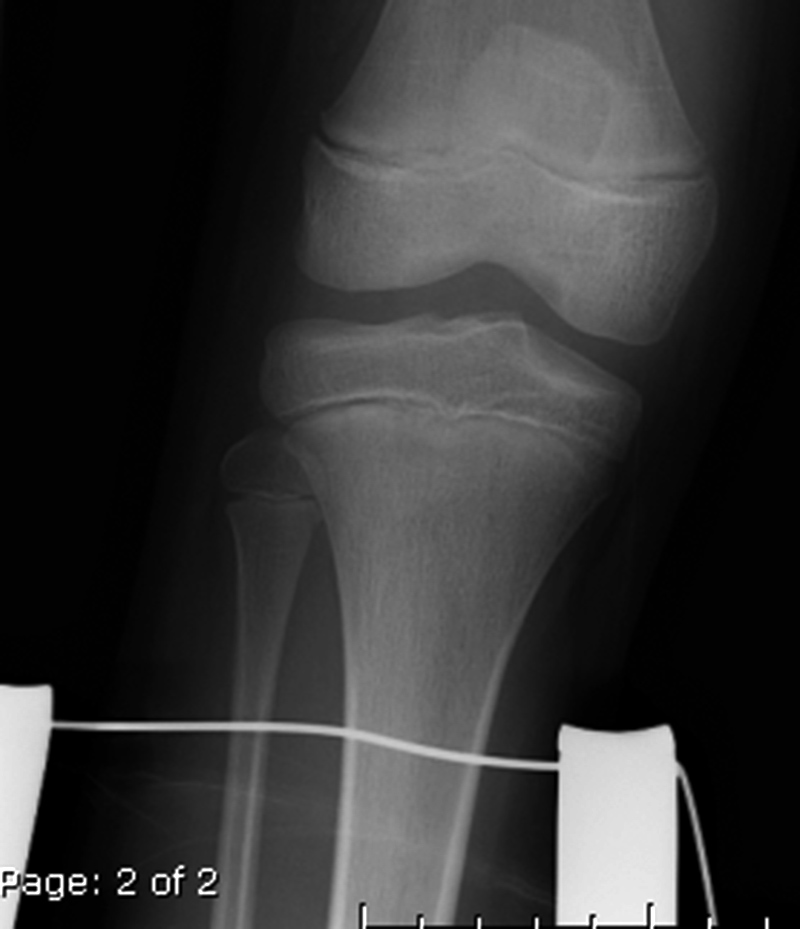

Hinged knee brace AP view Hinged knee brace lateral view K-wires in the distal radius K-wires in the wrist

65 year-old woman with healing patellar fracture stabilized by two cancellous partially threaded bone screws and tension band wires. 50 year-old woman with a distal radius fracture immobilized by 4 Kirschner wires (K-wires). There is also an ulnar styloid fracture.